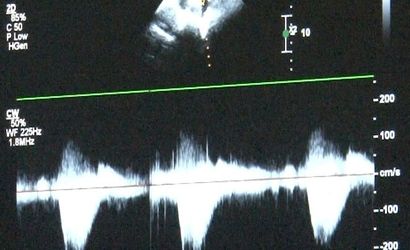

Erken tanı ve fetal ekokardiyografi

Kanuni Sultan Süleyman Eğitim ve Araştırma Hastanesi Çocuk Kardiyoloji Uzmanı Uzm. Dr. Damla Gökçeer Akbulut ve Sultangazi Haseki Eğitim ve Araştırma Hastanesi Çocuk Kardiyoloji Uzmanı Dr. Canan Yolcu erken tanının hayat kurtardığını aktarıyor. Fetal ekokardiyografi ile anne karnındayken doğumsal kalp hastalığı tespit edilebiliyor; böylece doğum sonrası erken müdahale şansı sağlanıyor. Uz. Dr. Gökçeer Akbulut, Sağlık Bakanlığı verilerine göre her yıl bin canlı doğumdan 8'inde doğumsal kalp hastalığı görüldüğünü hatırlattı.